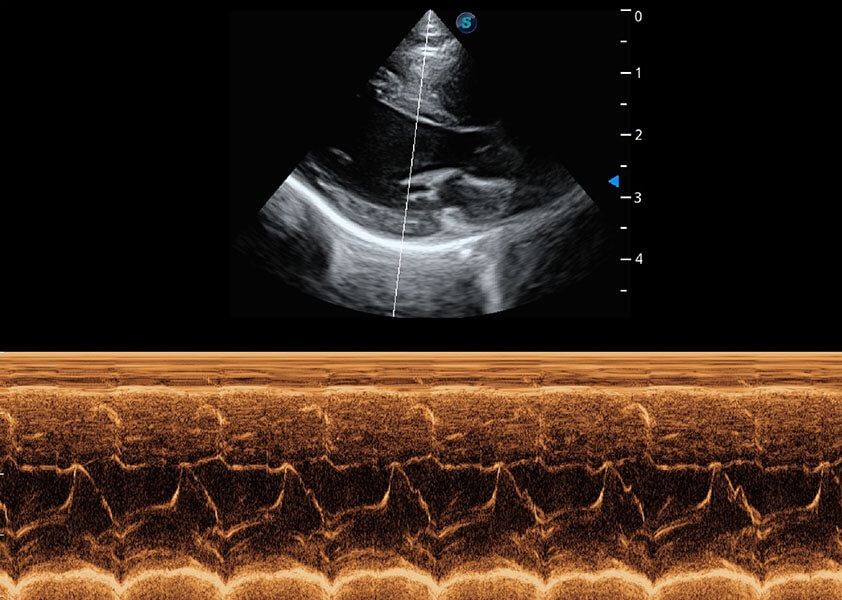

ProPet 60 作為一款高端臺式動物超聲設(shè)備,為動物醫(yī)生的日常診斷提供了一系列貼合動物臨床需求、解決臨床實際問題的高級成像功能。憑借全系列高清探頭,滿足醫(yī)生對腹部、心臟、生殖、淺表、肌骨等成像的所有需求,切實幫助您提升檢查效率,提高診斷信心。

獸用彩色多普勒超聲診斷系統(tǒng)